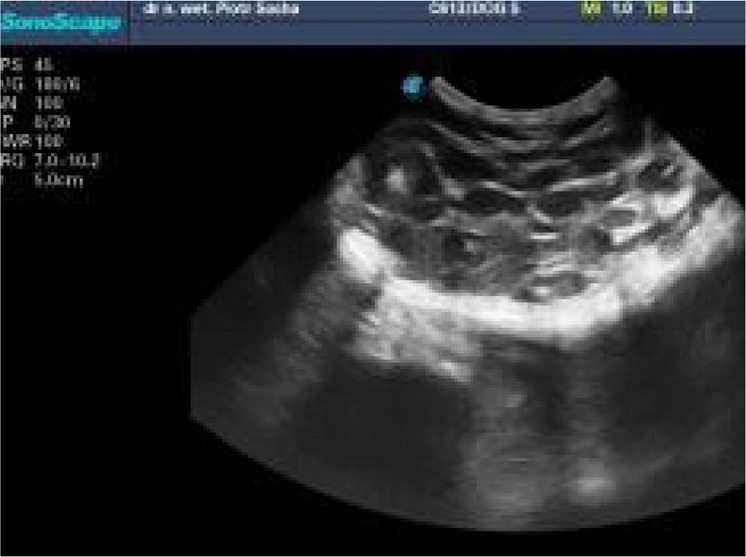

One of the disorders of the mammary gland in the queen is feline mammary fibroadenomatous hyperplasia (FMFH), caused by an increasing concentration of progesterone (P4) and some other local growth factors. It occurs mostly during puberty after the heat characterised by spontaneous or provoked ovulation, as a result of exogenous progesterone intake and sometimes during pregnancy. To diagnose a 14-month-old intact Maine Coon queen with extensive mammary gland hyperplasia, a clinical examination, analyses of the progesterone (P4) concentrations and ultrasound examination were performed. Feline mammary fibroadenomatous hyperplasia associated with a high P4 concentration after spontaneous ovulation was confirmed. After 24 days of therapy with a progesterone antagonist, aglepristone, the symptoms of FMFH resolved. After the next eight weeks, the queen was mated after the owner's decision. In the third week of pregnancy, a relapse was detected (mammary gland enlargement, pain, discomfort). At the same time, no abnormalities in the uterus or embryos were detected via ultrasound. The P4 concentrations were under regular control. For the next two weeks, only conservative treatment with NSAIDs was used. The queen spontaneously delivered six kittens without any difficulties or perinatal complications 67 days after the first mating. The cat previously treated with aglepristone for FMFH was successfully bred, but FMFH symptoms returned when progesterone concentrations increased during pregnancy.